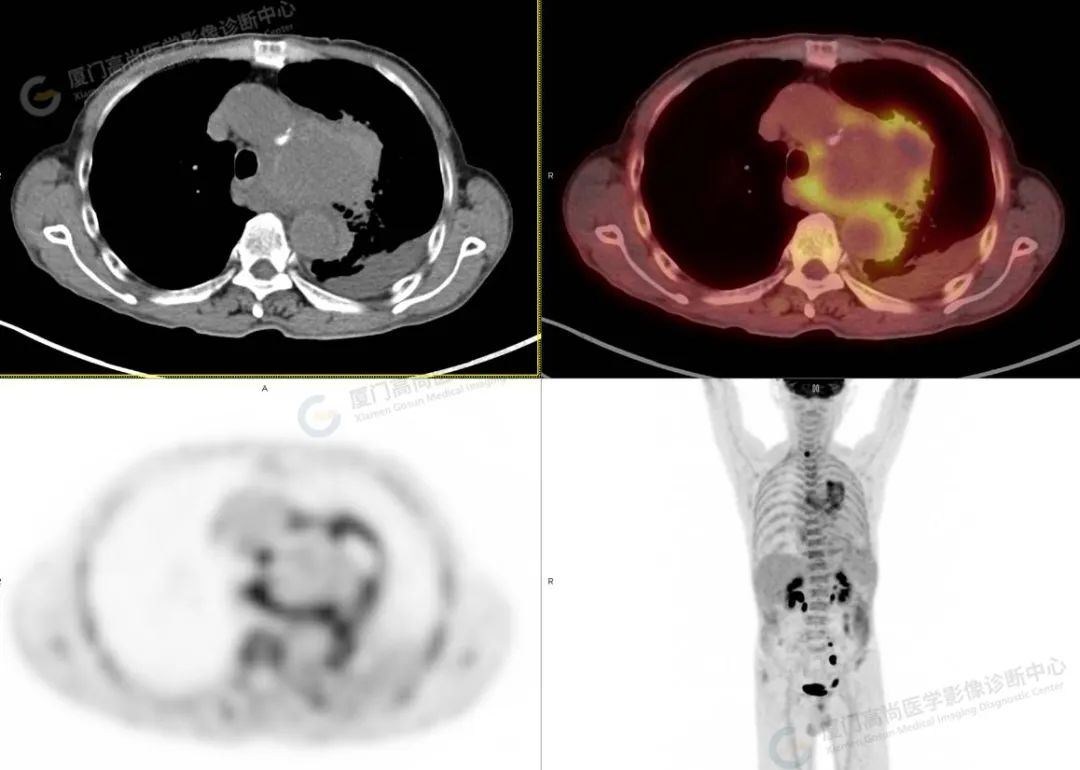

影像诊断:主动脉弓部瘤样扩张,并钙化斑内移,中心部位代谢减低,周围部分代谢增高,考虑主动脉夹层或动脉瘤破裂可能,并左侧胸腔积血、积液,动脉硬化,请结合临床及主动脉 CTA 进一步检查明确。

本中心发现王先生属于主动脉夹层或者主动脉瘤破裂可能,属心血管疾病的灾难性危急重症,如不及时诊治,48 小时内死亡率可高达 50%,故立即与其主管医师联系,并录制图像视频传达至医师,建议行主动脉 CTA 检查明确。后紧急行胸腹主动脉 CTA 示:主动脉弓假性动脉瘤形成伴边缘机化性血肿,并左侧胸腔包裹性积液、积血。